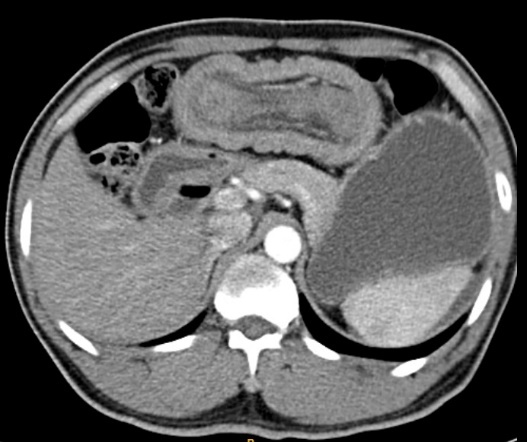

Khám lâm sàng thấy:  Đau bụng vừng thương vị, bụng mềm, phản ứng thành bụng (-), mass mơ hồ vùng thương vị. Chụp Xquang bụng không chuẩn bị tư thế đứng (Không thấy liềm hơi dưới cơ hoành 02 bên, không thấy hình ảnh mức hơi dịch điển hình). Kết quả siêu âm bụng: Vùng thượng vị có hình ảnh búi lồng kích thước # 5,1x7,1x10,3 cm. Bệnh nhân được chỉ định chụp CT scanner ổ bụng kết quả: Hình ảnh lồng ruột non vùng thượng vị dài trên 30cm với hình ảnh bia bắn và bánh mỳ kẹp thịt(Hình 1 và 2).Xét nghiệm công thức máu có: Bạch cầu 6,8 G/L, neurophile 74%. Thiếu máu với Hb: 84g/l, Hct: 28%, MCV: 67,74 fl, 20,16 pg, Tiểu cầu: 291G/l.

Hình 1. Hình ảnh bia bắn